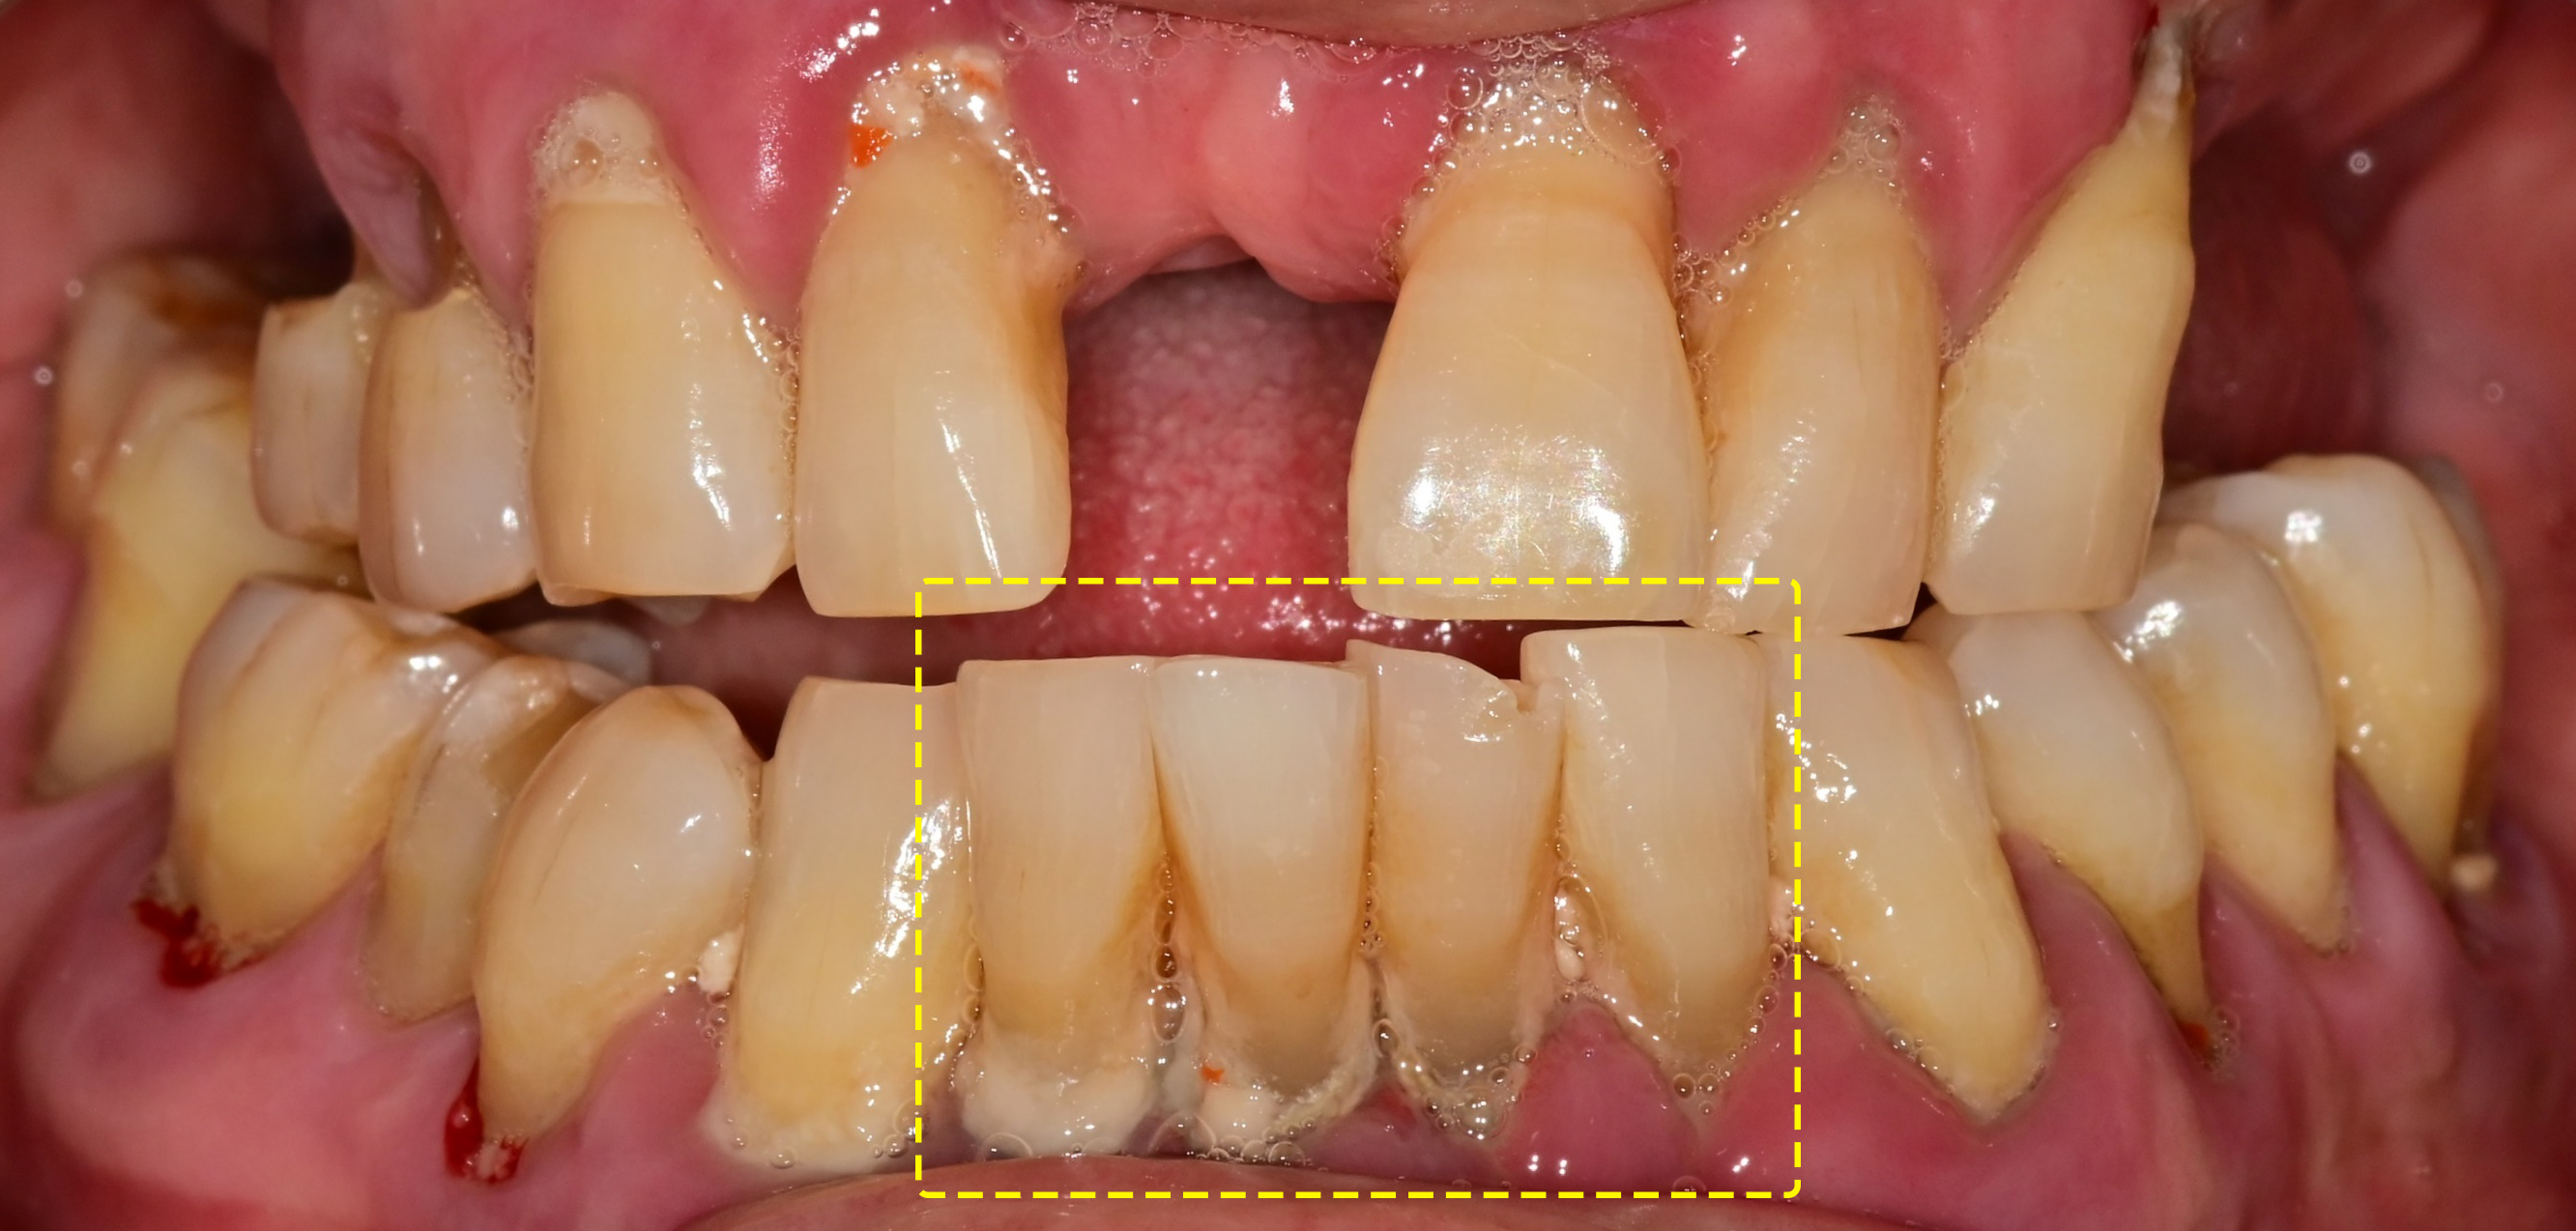

• STEP 01

수술부위